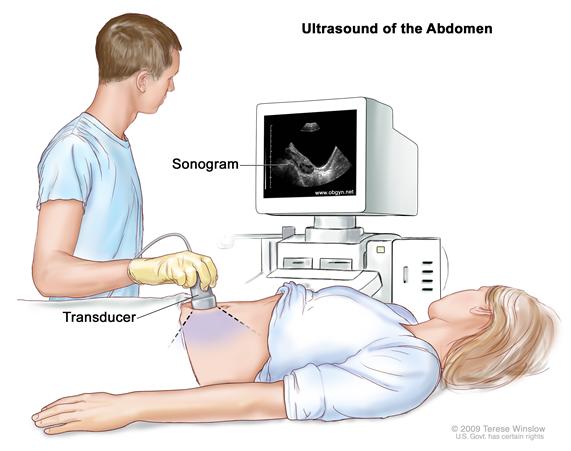

- Biologic Effects of Ultrasound in Healthcare Setting The instrument performing the emission of the sound waves and the recording of their bouncing back is referred to as the transducer and the medical practitioner generally gently presses the transducer against the skin of […]

- Ultrasound Scanning: Diagnosing Health Conditions The calculation is based on the time taken by the wave to return by measuring the distance, mass, nature, and stability of the object hit.